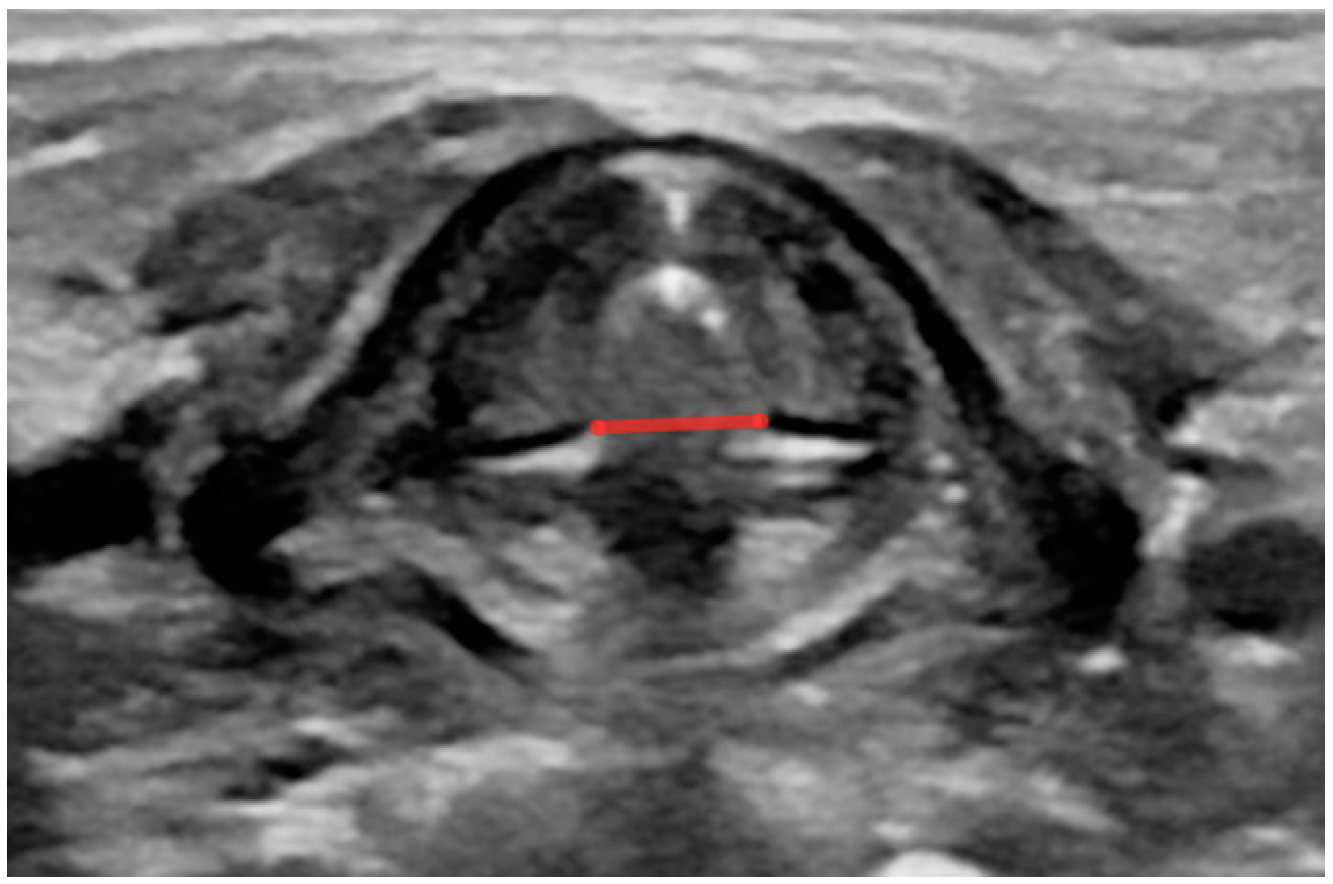

- Width of the glottis during calm breathing (measured in the transverse plane with lines drawn between two medial margins of arytenoid glands when they are farthest apart during breathing) (Figure A5);